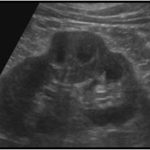

3-Duplex kidney

هذا مصطلح واسع يشمل عدة متغيرات منها وجود كليتين ملتصقات ببعض أو وجود two collecting systems في كلية واحدة. وهذه أيضا يوجد بها متغيرات أخرى من ناحية وجود حالب واحد أو حالبين ووجود شريان واحد أو اثنين.

يوجد هذا المتغير في قرابة ١٠٪ من الناس الطبيعيين. ويجب على الأخصائي التأكد من عدم توسع الحالبين وأيضا عدم وجود انسداد في أحد collecting systems وتحديدا العلوي.